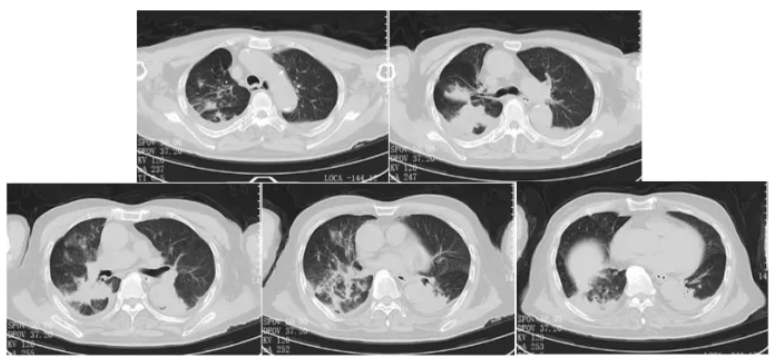

5. 随访结果

2025年2月26日患者门诊复查,未吸氧下氧饱和度正常,胸部CT示双肺感染病灶基本吸收,仅残留少许纤维条索影(图10)。

图10 出院后随访胸部CT(2025-02-26)